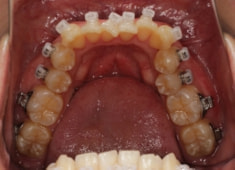

治療開始時